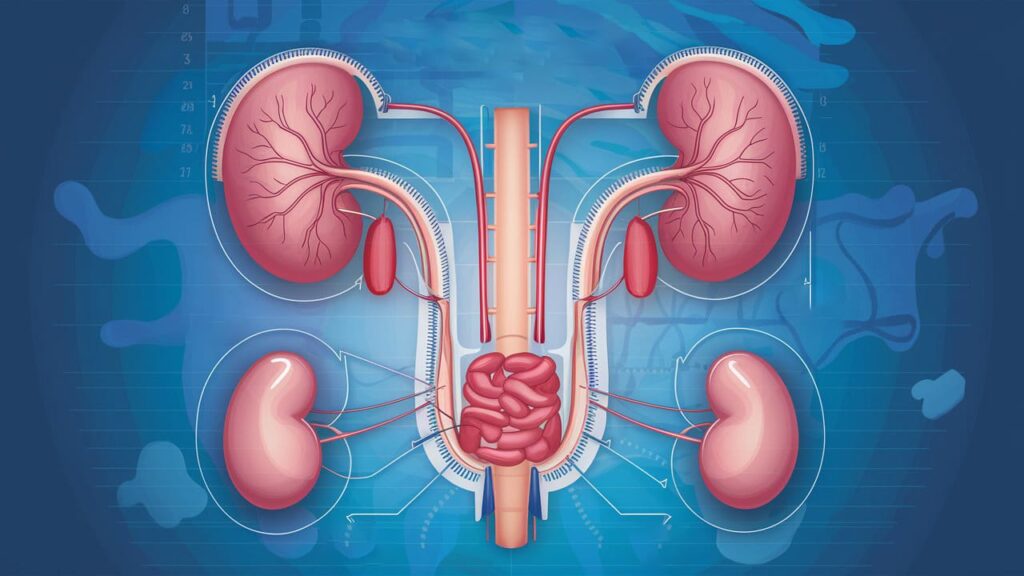

Urology

Our Urology Clinic at Mildmay Hospital Uganda provides expert diagnosis and treatment for conditions affecting the urinary tract and male reproductive system. We are committed to offering safe, confidential, and compassionate care for both men and women.

Ultrasound and Diagnostic Tests

Imaging and lab tests to assess urinary and reproductive health.